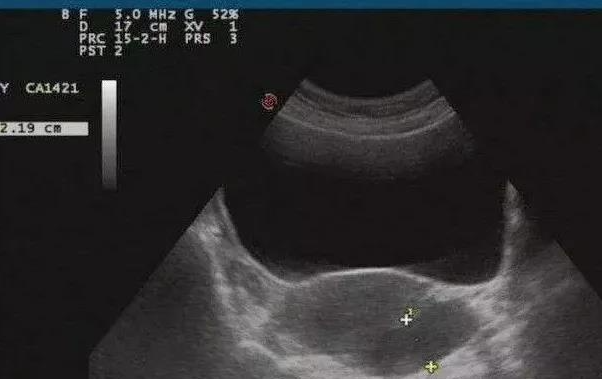

盆腔积液是什么?

盆腔炎、附件炎或子宫内膜异位症都可能引起盆腔积液,按病理因素可分为「生理性盆腔积液」和「病理性盆腔积液」。